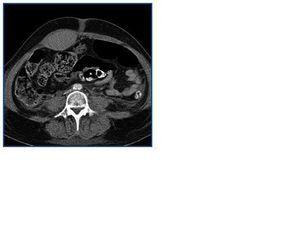

Tratada con metilprednisolona, ciclofosfamida y plasmaféresis (anticoagulación con citrato y reposición inicialmente con albúmina y posteriormente combinada con plasma) persiste deterioro de función renal con creatinina de 8,4 mg/dl y oliguria iniciándose hemodiálisis sin heparina. A los 13 días presenta dolor en higastrio y fosa iliaca izquierda tras un episodio de tos. Aparece una masa abdominal y anemización de 4 puntos. El TAC abdominal objetiva un hematoma de la vaina del recto anterior izquierdo (Figura 1). Se trasfunden 3 concentrados . El estudio de coagulación incluyendo factores es normal excepto Yvy de 10 minutos. Tres días después nuevo dolor en fosa iliaca derecha, con íleo paralítico y anemización de 3 puntos. El TAC objetiva un hematoma en ambos músculos rectos anteriores que se extiende hacia el espacio de Retzius y pelvis (Figura 2). Precisa 4 concentrados de hematíes. Se consulta con el servicio de cirugía y radiología intervencionista decidiendo tratamiento conservador expectante y asociar antibióticos (amoxicilina clavulánico) así como nutrición parental.

Figura 1.